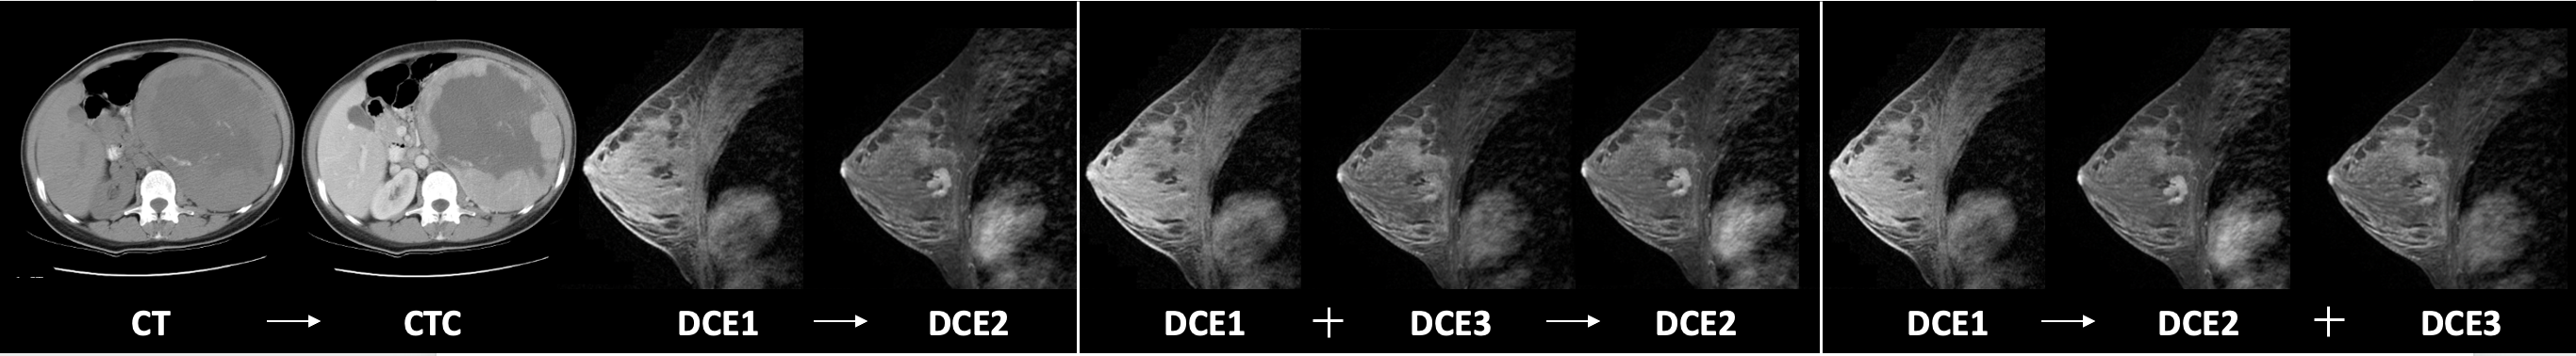

To comprehensively evaluate different generative models, we design benchmark tasks that reflect both increasing levels of difficulty and common clinical scenarios of missing modalities. As illustrated in fig. 2, we consider three representative settings:

1-to-1 Translation: Single input modality to a single target (e.g., CT CTC or DCE1 DCE2). This setting tests a model’s ability to capture modality-specific features and preserve one-to-one anatomical correspondences.

N-to-1 Translation: Multiple input modalities to a single target (e.g., DCE1, DCE3 DCE2). This evaluates how well models integrate complementary anatomical information across sequences while maintaining structural fidelity and modality consistency. In DCE imaging, this setting further corresponds to reconstructing an intermediate phase from its neighbors, thereby probing whether models can capture the temporal dynamics of contrast uptake.

1-to-N Translation: A single input modality to multiple targets simultaneously (e.g., DCE1 DCE2, DCE3). This setting assesses whether models can jointly capture inter-modal dependencies and generate anatomically consistent outputs across domains. Clinically, it is relevant for scenarios where only an early phase or a non-contrast scan is acquired, and later phases must be synthesized to approximate the full dynamic sequence.